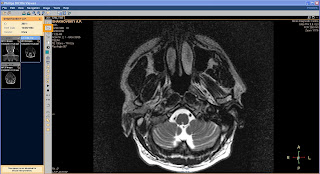

После загрузки наборов данных вы увидите в окне слева значки наборов данных, а справа в главном окне одно увеличенное изображение. Изначально будет выделен первый сверху значок. Выберите нужные вам данные для исследования и щелкните по соответствующему значку. В главном окне отобразится первое изображение выбранных данных, и вы можете приступать к исследованиям.

Вращайте колесо мыши и последовательно просматривайте изображения.

Функция интерактивного кино позволяет производить вручную прокрутку изображений перемещая мышь. Для начала работы в режиме интерактивного кино в панели инструментов щелкните по соответствующему значку.

другой формат файла, например, BMP, JPEG, AVI и экспортировать их в систему файлов

Чтобы увидеть информацию о пациенте из Dicom заголовка щелкните по значку

Для печати выбранного изображения щелкните в горизонтальной панели инструментов по левому значку